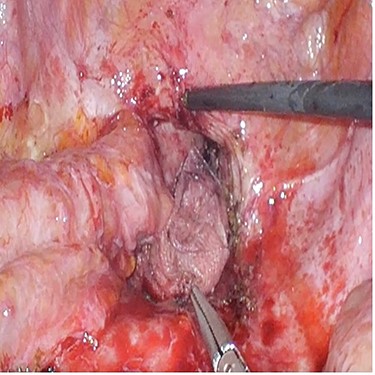

A 42-year-old man with perianal abscess and fistula due to low rectal cancer had completed long-course radiotherapy but was unable to complete FOLFIRI regimen due to elevated liver enzymes because of his underlying chronic hepatitis B. He underwent robotic-assisted abdominoperineal resection (APR) 6 weeks later. Mesh placement was performed laparoscopically after placing transabdominal pelvic drain (Fig. 1). He developed perineal wound infection on postoperative day 4 requiring wound dressings and antibiotics. He was discharged 17 days after surgery but was readmitted 28 days after initial operation for presacral abscess requiring percutaneous drainage. Subsequent CT abdomen showed resolution of presacral collection. Histopathological examination showed moderately differentiated adenocarcinoma ypT3N0M0. He completed adjuvant capecitabine and after 12.5 months, there was no evidence of unhealed perineal wound or small bowel descent.

Case 2—laparoscopic picture of Gore-Tex Dual Mesh placed at the pelvic inlet with the microporous smooth side facing the abdominal cavity.